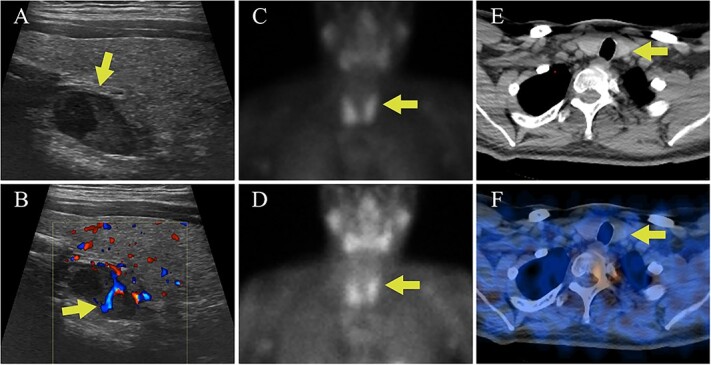

Germline and somatic pathogenic variants in the CDC73 gene, encoding the nuclear protein parafibromin, increase the risk for parathyroid carcinoma and cause hereditary primary hyperparathyroidism (PHPT) syndromes known as familial isolated hyperparathyroidism (FIHP) and hyperparathyroidism-jaw tumor syndrome (HPT-JT). The identification of pathogenic germline variants in PHPT-susceptibility genes can influence surgical planning for parathyroidectomy, guide screening for potential syndromic manifestations, and identify/exonerate at-risk family members. Numerous types of pathogenic germline variants have been described for CDC73-related conditions, including deletion, truncating, missense, and splice site mutations. Here, we report identification of a non-coding germline CDC73 variant (CDC73 c.1155-3A > G), previously categorized as a variant of uncertain significance (VUS), in a family with HPT-JT. This variant, found in two family members with PHPT, altered CDC73 splicing in peripheral blood cells and disrupted parafibromin immunostaining in associated parathyroid adenomas, strongly evidencing its pathogenicity. Sestamibi scintigraphy yielded nondiagnostic localization results for both patients' parathyroid adenomas, consistent with prior studies suggesting lower sensitivity for small or cystic lesions. Our findings demonstrate key aspects of CDC73-related disorders, highlight the diagnostic value of RNA testing, and exemplify the importance of obtaining a thorough, three-generational family history.